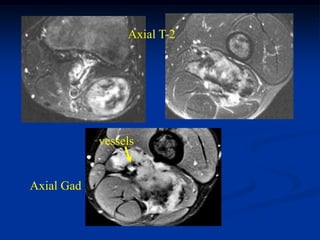

15 year female with painful enlarging desmoid past 6 months

while on chemotherapy

Coronal Gad shows minimal response to chemotherapy

Axial T-2

vessels

Axial Gad

Cor T-2        Two Cor gad              Sag gad